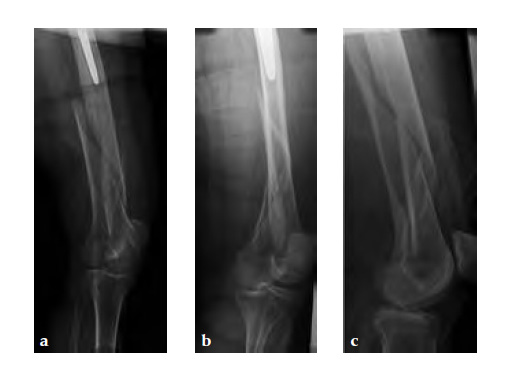

The 3.5 Locking Attachment Plate which can be attached to an LCP offers an alternative to cables (Fig 1). With the possibility to insert 3.5 mm locking screws bicortically by avoiding the prosthesis stem (Fig 2) a similar or even better mechanical stability than with cables can be reached with a less invasive procedure. The plate is attached to a base plate, in essence, widening that plate and its screw angle options to gain 3.5 mm screw purchase around a prosthesis or any device that may be blocking the intramedullary canal.